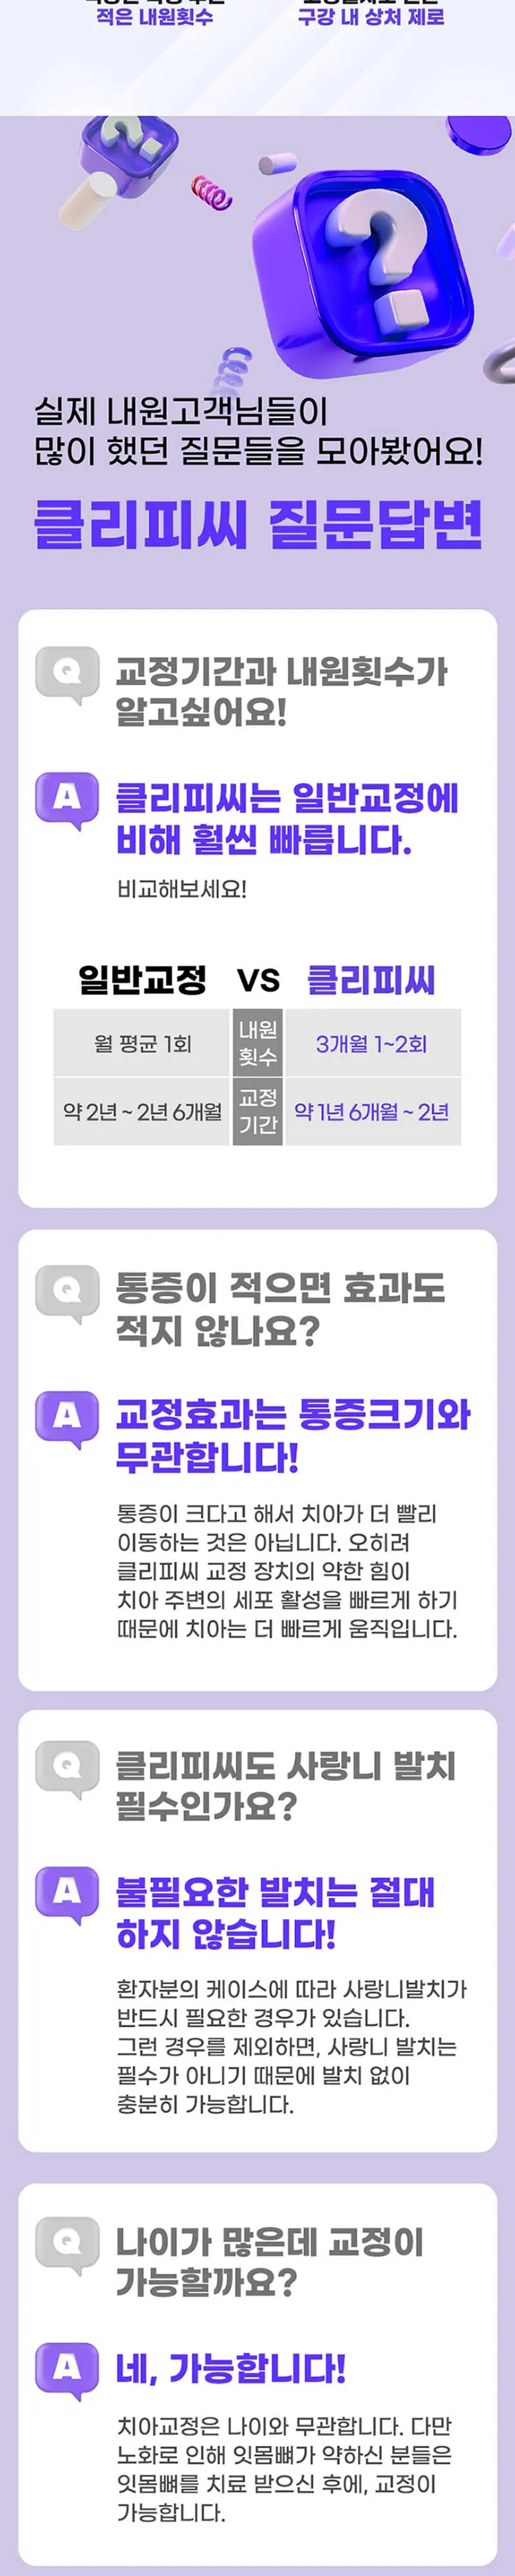

上の歯が不正咬合で、噛むと下の歯とぶつかり、年齢を考えて矯正を始めることにしました。いくつかの病院で相談を受けましたが、イベントに合わせて一番安いところを選び、病院も新しく、最新設備とアクセスの良さからこちらで進めました。上の歯に矯正器具を装着した後、1週間後に下の歯を装着しましたが、慣れてくると不快感はなくなりました。矯正管理をし、必要なワックスや歯間ブラシセットも頂きました。月に一度定期的に訪問して、歯の検診や矯正器具のチェックを受け、広がっていた歯が整うにつれて、顎の部分もすっきりし、ダイエット効果も感じています。医師も親切で、手早く進めてくれるので嬉しいです。一括での支払いが必要で負担に感じましたが、ソウル愛商品券で支払いができるので、より安く進められるのが良かったです。もっと早くやっておけばよかったと思います。